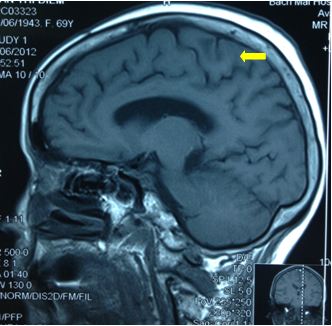

Hình 6: Hình ảnh chụp MRI sọ não sau 6 tháng xạ phẫu bằng dao gamma quay: Khối u não di căn vùng đỉnh trái tan hoàn toàn

Chụp MRI sọ não: Sau xạ phẫu 6 tháng bằng dao gamma quay: khối u não tan biến hoàn toàn

Trước điều trị: u 20×19mm

Sau điều trị 6 tháng: u tan hoàn toàn